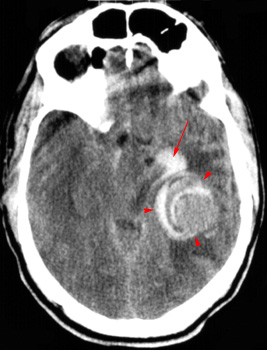

Head CT > Stroke > Hemorrhage Due to AM

Hemorrhage Due to Arteriovenous Malformation

An underlying arteriovenous malformation (AVM) may or may not be visible on a CT scan. However, prominent vessels adjacent to the hematoma suggest an underlying arteriovenous malformation. In addition, some arteriovenous malformations contain dysplastic areas of calcification and may be visible as serpentine enhancing structures after contrast administration.